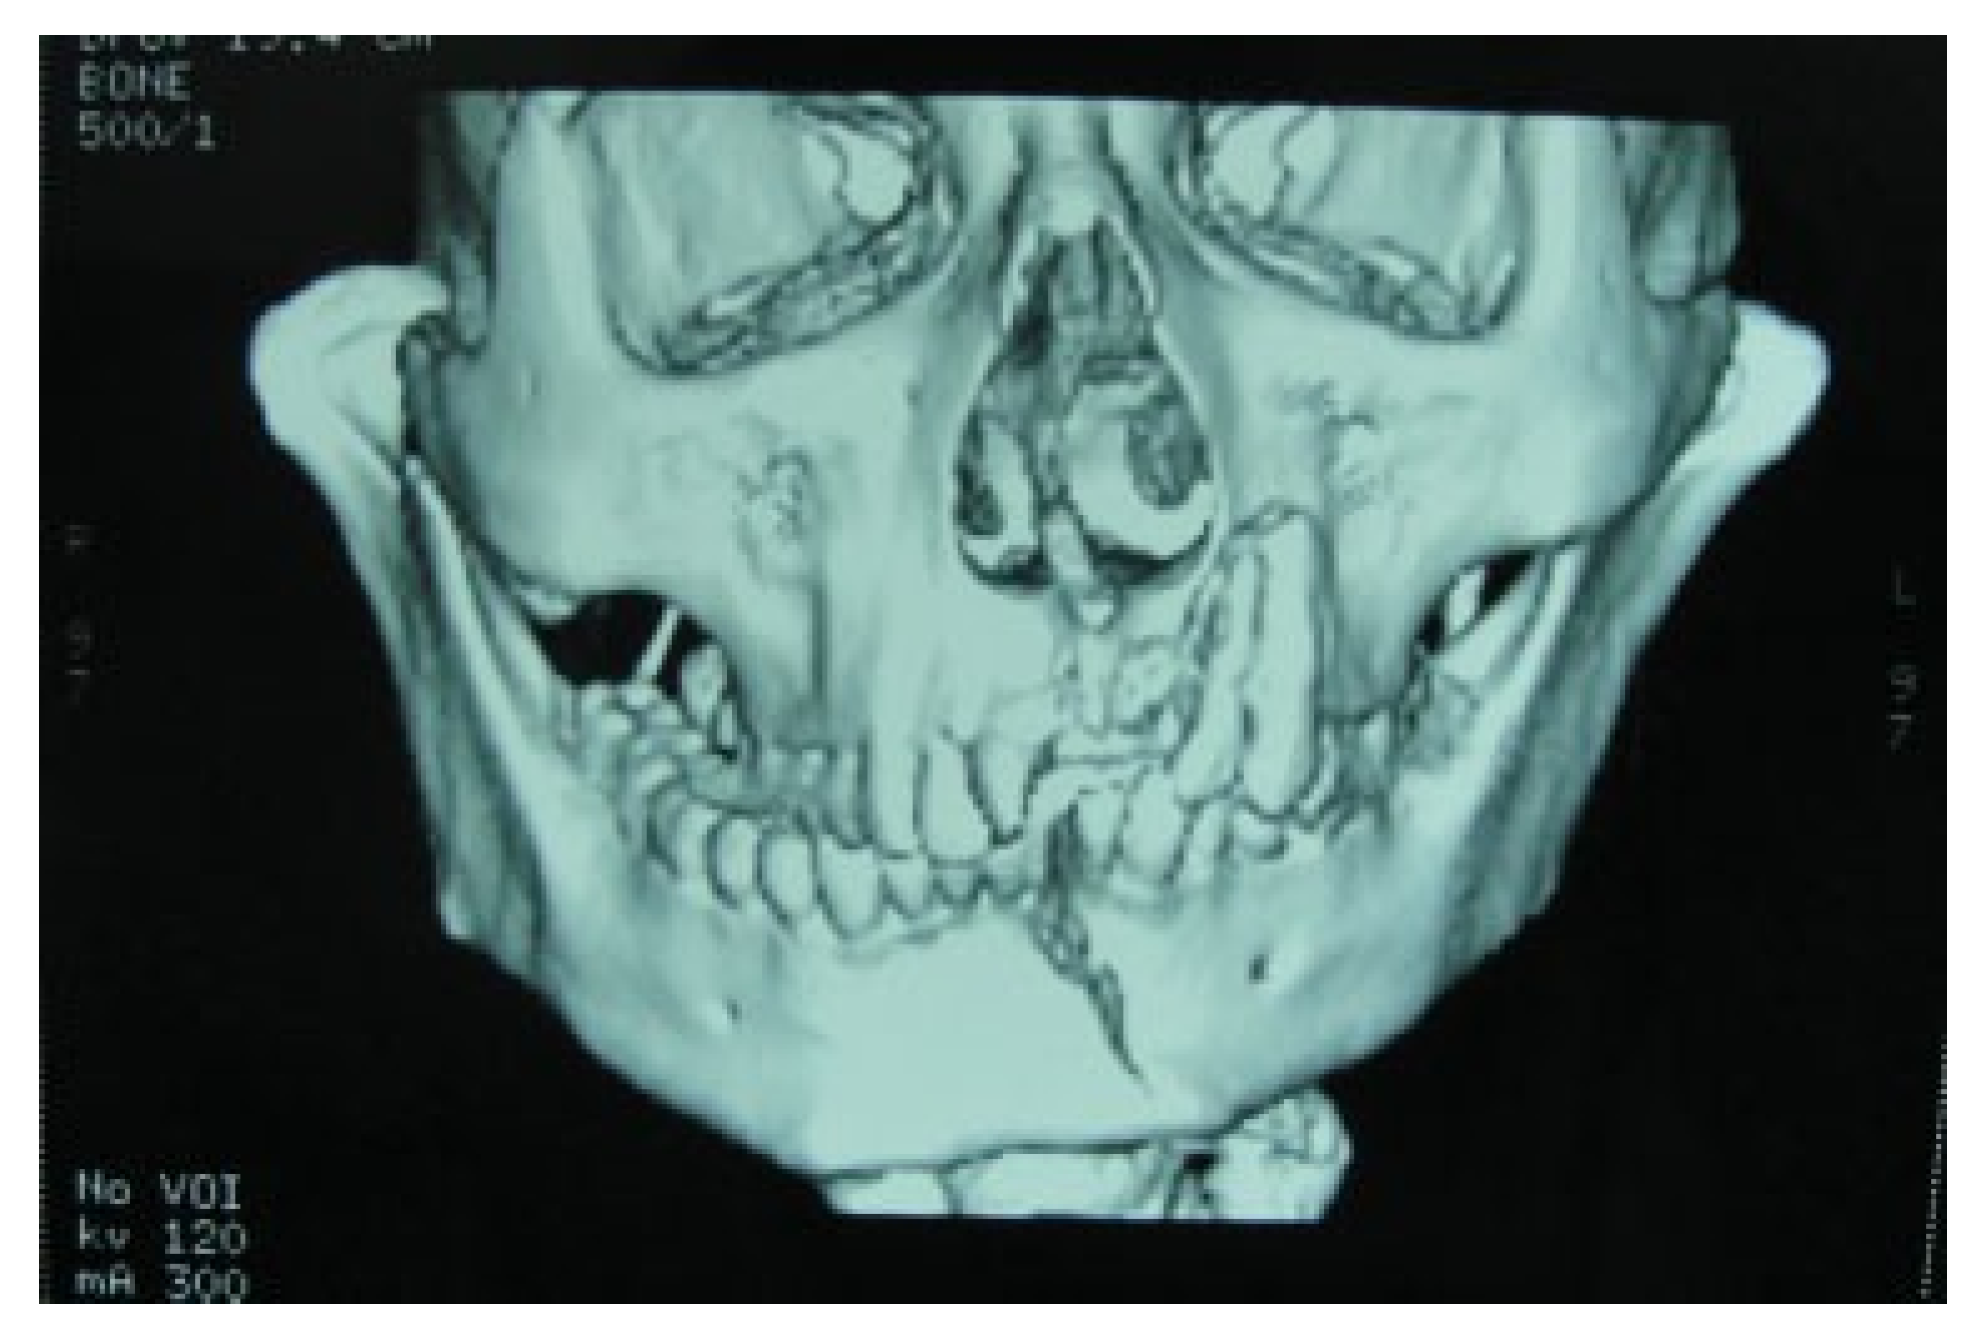

:1. Case Report